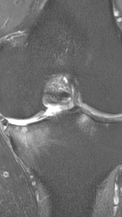

Рецидивирующий бурсит коленного сустава

Излечение за 2 процедуры ФДТ Ревиксан